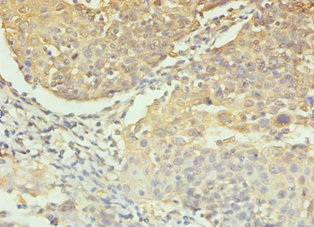

Immunohistochemistry of paraffin-embedded human colon cancer using CSB-PA05689A0Rb at dilution of 1:100